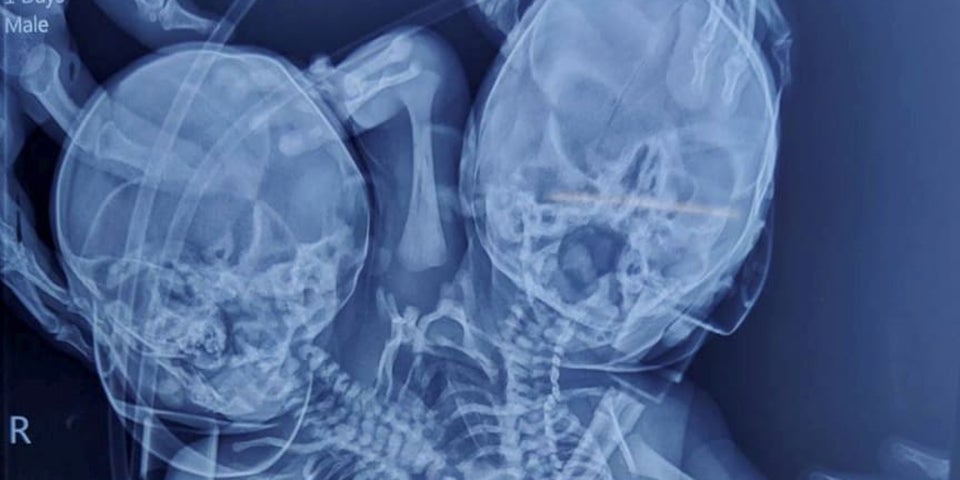

Das Baby wurde mit zwei Köpfen, zwei Wirbelsäulen, zwei Herzen und drei Armen geboren.